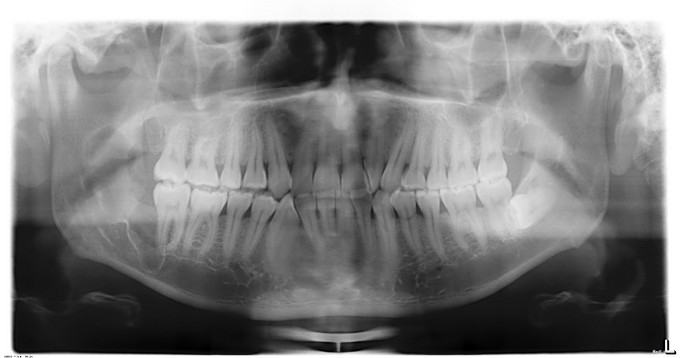

双侧颜面部基本对称,右下颌未见明显隆起,表明皮肤无异常,皮温无升高,无压痛,无右下唇麻木,无张口受限,开口度4.0cm,开口型"↓",双侧髁突动度一致,开闭口未闻及关节明显弹响音。口内检查:右下8未萌,牙齿无松动,无叩痛,右下颌未见明显隆起,无瘘道,双侧头颈部无扪及明显肿大淋巴结。我院CT检查:右下8埋伏于骨内,牙冠偏远中,牙根偏近中,根尖突向下颌神经管。右下8区至右下颌升支近乙状切迹下方见类椭圆形骨质密度减低影,边界清楚,大小约4.4*1.5*.8cm,边缘见骨质增生。其内包含右下8牙冠。肿物膨胀尚不明显,右下8区牙槽嵴顶骨质吸收消失。病变下方紧邻下颌神经管,局部管壁吸收。提示:右下颌骨囊肿:牙源性角化囊性瘤?

初 步 诊 断: 1.右下颌骨肿物待查:牙源性角化囊性瘤? 出 院 诊 断: 1.牙源性角化囊性瘤 2.48埋伏阻生牙 在手术室全麻下行右下颌升支肿物刮除+48复杂牙拔除术+右下颌骨区骨皮质术+邻近瓣转移修复术。术后予预防感染、消肿等对症治疗。